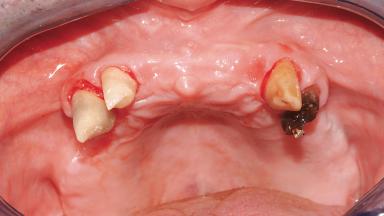

A 61-year-old male patient with a failing fixed maxillary rehabilitation and a fixed mandibular rehabilitation requested a new fixed maxillary rehabilitation. The patient was wearing a temporary metal-reinforced maxillary bridge inserted two years before the consultation. He reported that his previous dentist did not want to insert a definitive framework because he considered the residual teeth to have a negative prognosis. The patient reported a history of recurrent caries and endodontic complications as the main reason for the previous extractions. The anamnesis was negative for periodontal disease and bruxism. The patient’s chief compliant was the mobility of his maxillary prosthesis, which needed to be re-cemented frequently, and discomfort during chewing.Moreover, the patient was not satisfied with the esthetic appearance of his maxillary teeth, which he found too long. The patient asked for a stable and comfortable fixed maxillary rehabilitation and firmly rejected any removable solution.

Case Type Edentulous Maxilla

Jaw Maxilla

Area Full-Arch

# of Teeth All